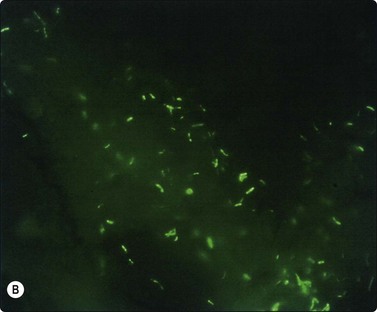

Negative images of mycobacteria may be seen in the background serum and cytoplasm of histiocytes in the Giemsa stain (Fig. 18.5), and the beaded 3–4-micron bacilli stain in the ZN (Fig. 18.6A) and auramine (Fig. 18.6B) stains and autoflouresce in the Papstain.41

image image

Fig. 18.6 (A) Curved beaded mycobacteria in Ziehl Neelsen stain (ZN, ×1000); (B) Mycobacteria in Auramine stain (Auramine, ×1000).